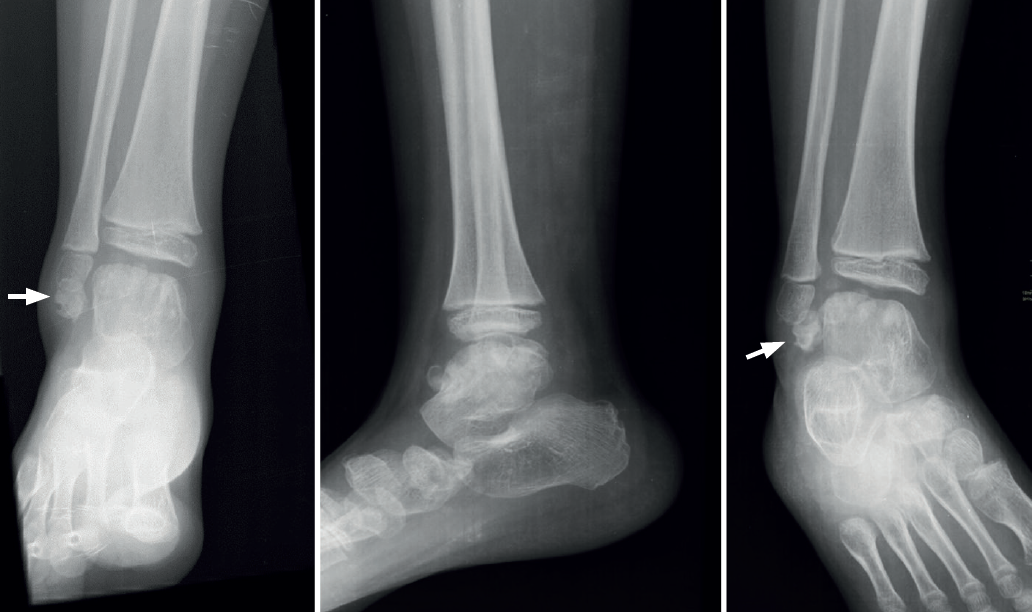

Se presentaría como una segmentación del astrágalo en el plano coronal con 2 fragmentos, uno anterior y otro posterior, separados por una hendidura o pseudoartrosis; a diferencia del os trigonum, el fragmento posterior se articula con la faceta articular posterior del calcáneo y en ocasiones también con la cara articular posterior de la tibia, pudiendo alcanzar un tamaño de un tercio o incluso más del volumen total (Figura 3); ambos fragmentos tendrían una estructura histológica similar(10).

Algunos autores lo han relacionado también con una infección neonatal(56). El aspecto radiológico puede aparentar una fractura y así relacionarse con microtraumatismos repetidos en la infancia o inestabilidad(57), aunque su principal característica es la articulación del fragmento posterior con el calcáneo , llegando a formar una prolongación en consola (Figura 8).

El talus bipartitus probablemente sea la alteración congénita del astrágalo más parecida al síndrome de Trevor. Es muy poco frecuente, registrándose en la bibliografía como casos aislados(54) o series muy cortas (4 o 5 casos), casi siempre en personas jóvenes, en las que no se pueden encontrar referencias a posible bilateralidad(55).

En su evolución suele presentar dolor, grados variables de afectación articular y edema óseo visible en los estudios por RM(10) que lleva a plantear tratamientos quirúrgicos en la serie de 4 casos de Rammelt et al.(58).